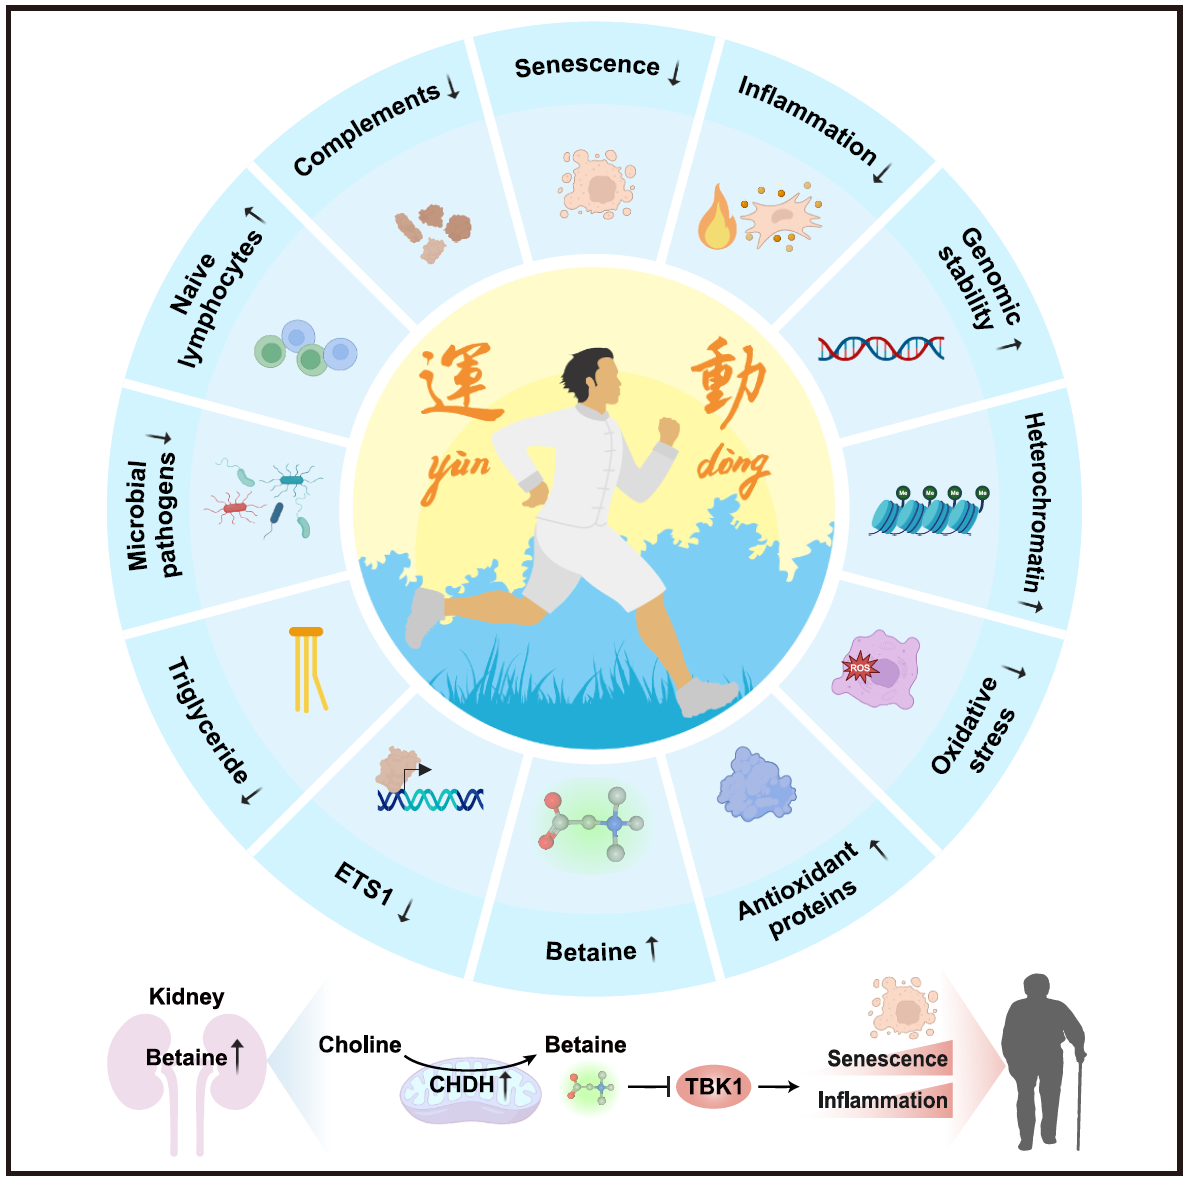

运动是良医!中医健身可以这么练